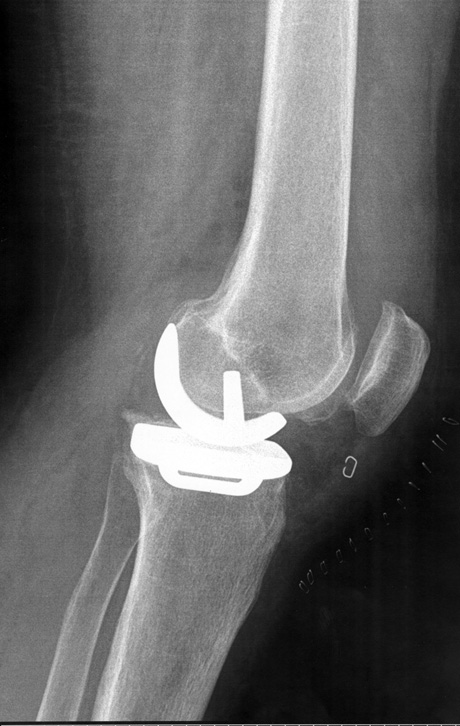

Ακτινολογική εικόνα της μονοδιαμερισματικής αρθροπλαστικής. Το υγιές τμήμα της άρθρωσης παραμένει ανέπαφο.

Μονοδιαμερισματική αρθροπλαστική Oxford Zimmer Biomet για την αντικατάσταση του έσω διαμερισματος της άρθρωσης του γόνατος το οποίο πάσχει από οστεοαρθρίτιδα.